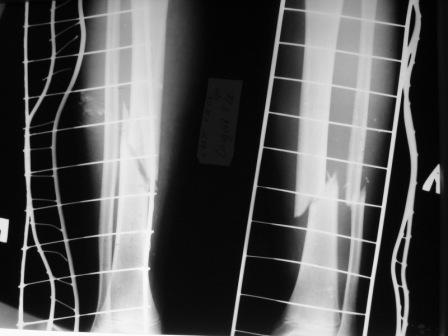

Поступил мальчик 12 лет с переломами диафиза костей обеих голеней. В связи с этим поставлен вопрос, который уже поднимался в узких кругах, но к однозначному решению это не привело. Можно ли в данном случае применить ЗИО с блокированием? Если использовать классическую точку входа над бугристостью и избежать блокирования в зонах роста повлияет ли это рост кости? Как с этим обстоят дела у иностранных колег?

Данных в поддержку блокируемого штифтования большеберцовой кости у детей не найдено (в отличие от бедра,встречаются статьи-от 6! лет). Зато среди причин GENU RECURVATUM указывается скелетное вытяжение в области бугристости большеберцовой кости, при незакрытой зоне роста. На предоставленых снимках зона роста апофиза закрыта шиной Беллера.